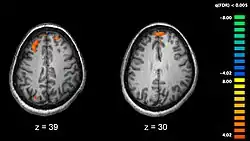

Recent research using neuro-imaging technology including PET and fMRI scanning has shown that there is an extensive amount of distributed brain activation during the process of episodic encoding and retrieval. Among the various regions, the two most active areas during the constructive processes are the medial temporal lobe (including the hippocampus) and the prefrontal cortex.[15] The Medial Temporal lobe is especially vital for encoding novel events in episodic networks, with the Hippocampus acting as one of the central locations that acts to both combine and later separate the various features of an event.[16][17] Most popular research holds that the Hippocampus becomes less important in long term memory functioning after more extensive consolidation of the distinct features present at the time of episode encoding has occurred. In this way long term episodic functioning moves away from the CA3 region of the Hippocampal formation into the neocortex, effectively freeing up the CA3 area for more initial processing.[17] Studies have also consistently linked the activity of the Prefrontal Cortex, especially that which occurs in the right hemisphere, to the process of retrieval.[18] The Prefrontal cortex appears to be utilized for executive functioning primarily for directing the focus of attention during retrieval processing, as well as for setting the appropriate criterion required to find the desired target memory.[15]